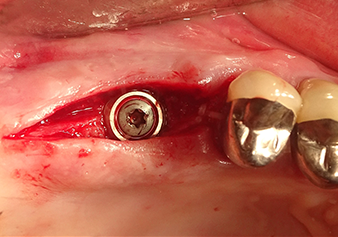

Une patiente de 49 ans, non fumeuse et sans antécédents médicaux remarquables, a été orientée vers notre cabinet de chirurgie orale pour l’extraction chirurgicale de la dent 16 préalable à la pose d’un implant. Après l’extraction, la patiente a rencontré de légers problèmes de sinusite, à la suite de quoi nous avons commencé par attendre six mois avant de prendre la mesure. À l’endroit prévu pour la pose de l’implant, l’os résiduel mesurait 3-4 mm de haut (Fig. 1 et 2).

Après la préparation atraumatique du lambeau muco-périosté, la position de l'implant est marquée à l'aide de l’insert I1 et le site préparé - jusqu’à la perception d’une résistance initiale. Les inserts de piézochirurgie sont utilisés suivant un mouvement ascendant et descendant, sans exercer aucune pression. La vibration piézoélectrique produit l’effet de cavitation souhaité, qui s’avère efficace.